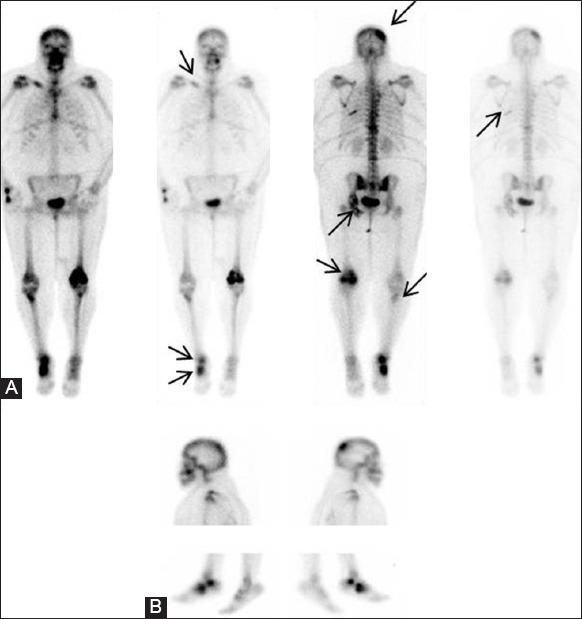

Sinus histiocytosis with massive lymphadenopathy (SHML) or Rosai-Dorfman disease is a non-neoplastic condition which typically presents as massive, bilateral cervical lymphadenopathy and can involve multiple extranodal organ systems such as skin, eyes, and upper respiratory tract in about 28% cases. Bone lesions in association with nodal disease are seen in less than 10% cases. Isolated bone involvement as the only manifestation of SHML is extremely rare, with less than 50 cases reported in the literature. We report a very uncommon case of Rosai-Dorfman disease with isolated multifocal osseous involvement as the only presenting feature, involving about 10 different sites with no lymphadenopathy or other organ system involvement.

伴巨大淋巴结病的窦性组织细胞增生症(SHML)或罗萨伊-多夫曼病是一种非肿瘤性疾病,通常表现为双侧巨大颈部淋巴结病,约28%的病例可累及多个结外器官系统,如皮肤、眼睛和上呼吸道。与淋巴结疾病相关的骨病变见于不到10%的病例。孤立性骨受累作为SHML的唯一表现极为罕见,文献报道不足50例。我们报告了一例非常罕见的罗萨伊-多夫曼病病例,其唯一的表现为孤立性多灶性骨受累,累及约10个不同部位,无淋巴结病或其他器官系统受累。